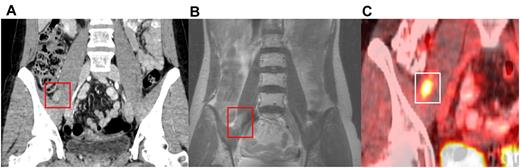

Given the wide variety of sites in which MS develops, imaging can facilitate diagnosis and monitor treatment response. MS often appears as a soft-tissue mass best suited to imaging by computed tomography (Figure 3A).67 Positron emission tomography can also be used (Figure 3C) and is particularly helpful for radiation therapy (RT) planning68 and monitoring response to treatment (Figure 4). When MS develops in the CNS, magnetic resonance imaging is useful.69 MS uniformly enhances with gadolinium, which should be administered when there are no contraindications (Figure 3B).67 The radiographic appearance of MS was recently reviewed by Fritz et al with many representative images provided.70 In our practice, computed tomography is routinely performed with consideration of a combined positron emission tomography scan if RT is planned.

Radiographic appearance of MS. MS along with the path of the right femoral nerve on (A) coronal computed tomography imaging, (B) coronal axial T1 postmagnetic resonance imaging, and (C) positron emission tomography.